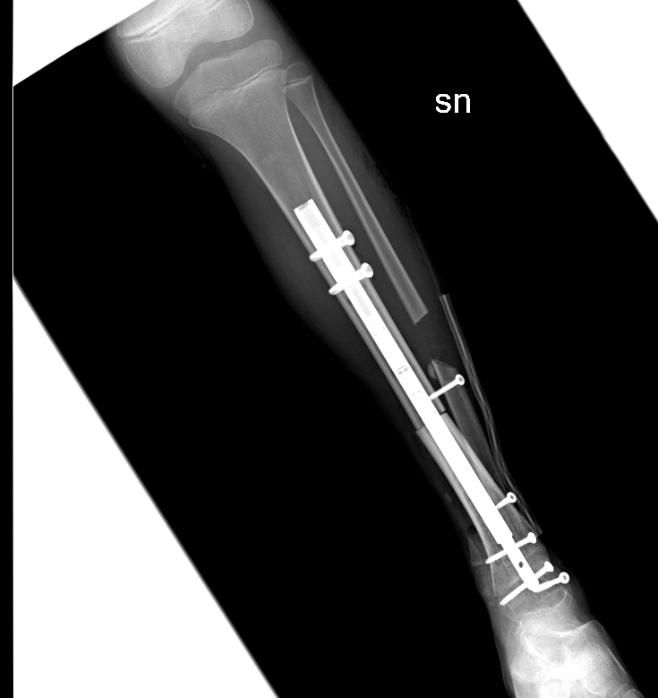

Prima volta al mondo: una bimba di 9 anni ha una nuova caviglia grazie all'osso di un donatore e un chiodo allungabile. E tornerà a camminare

Al Regina Margherita ricostruita l'articolazione a una piccola paziente affetta da una rarissima forma di tumore alle ossa